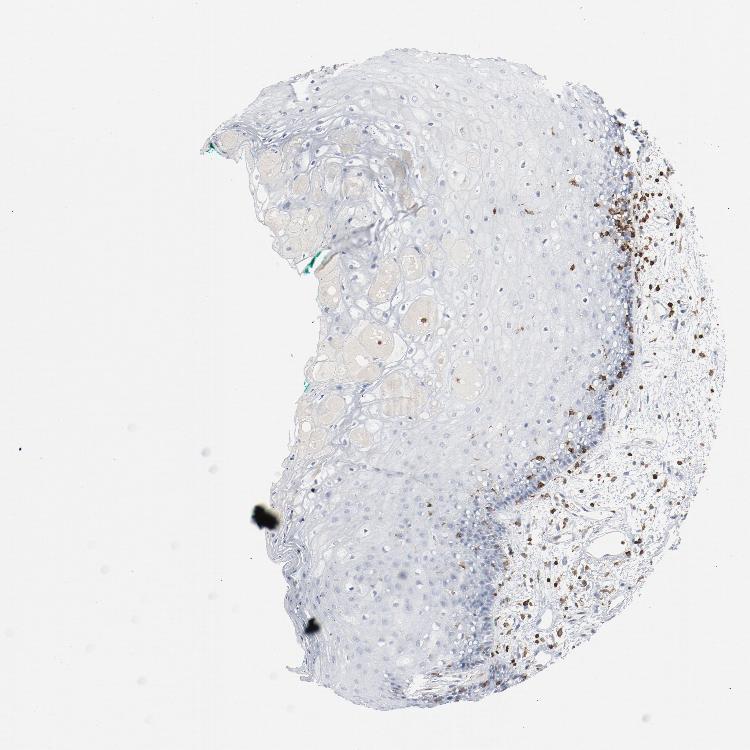

TISSUE PRIMARY DATA ORAL MUCOSA Show tissue menu

ORAL MUCOSA - Antibody stainingi

Antibody staining in the annotated cell types in the current human tissue is reported as not detected, low, medium, or high, based on conventional immunohistochemistry profiling in selected tissues. This score is based on the combination of the staining intensity and fraction of stained cells.

Each image is clickable and will lead to virtual microscopy that enables deeper exploration of all samples and also displays staining intensity scores, fraction scores and subcellular localization as well as patient and tissue information for each sample.

Antibody HPA036396Antibody HPA036397Antibody CAB004574

Squamous epithelial cells Not detectedNot detectedNot detected